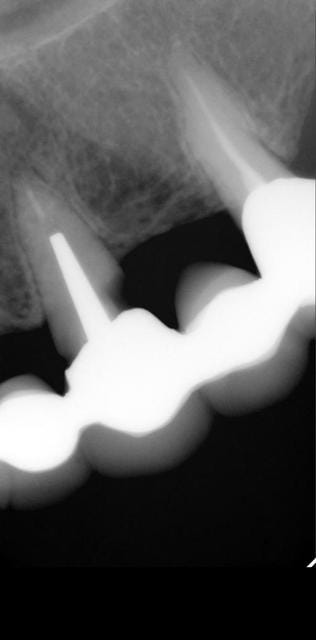

J'ai besoin d'avis éclairés pour une patiente dont voici la situation initiale:

- Femme de 83 ans qui consulte pour le rescellement de 44 avec 43 en extension collé au gros composite sur 42.

Voici le compte -rendu de mon bilan:

. Maxillaire: 18 incluse

- bridge 16 à 12 (sans 15) avec carie sur 13 et 12 vitale (ou du moins pas d'endo)

- couronne sur 11

- bridge 21 à 25 avec caries sur 21 et 23

- 27 RAS, absence de 17 et 26 non remplacées

.Mandibule: 44/43 à refaire, 35 à 37 non remplacées, crête pas très épaisse derrière 34, problème paro (présence de tartre)

Les bridges du haut sont donc perdus, 13, 21 et 23 à extraire, dents restantes ensuite: 16,12,11,25,27

Je vous met les radios et j'attend vos avis avec impatience.